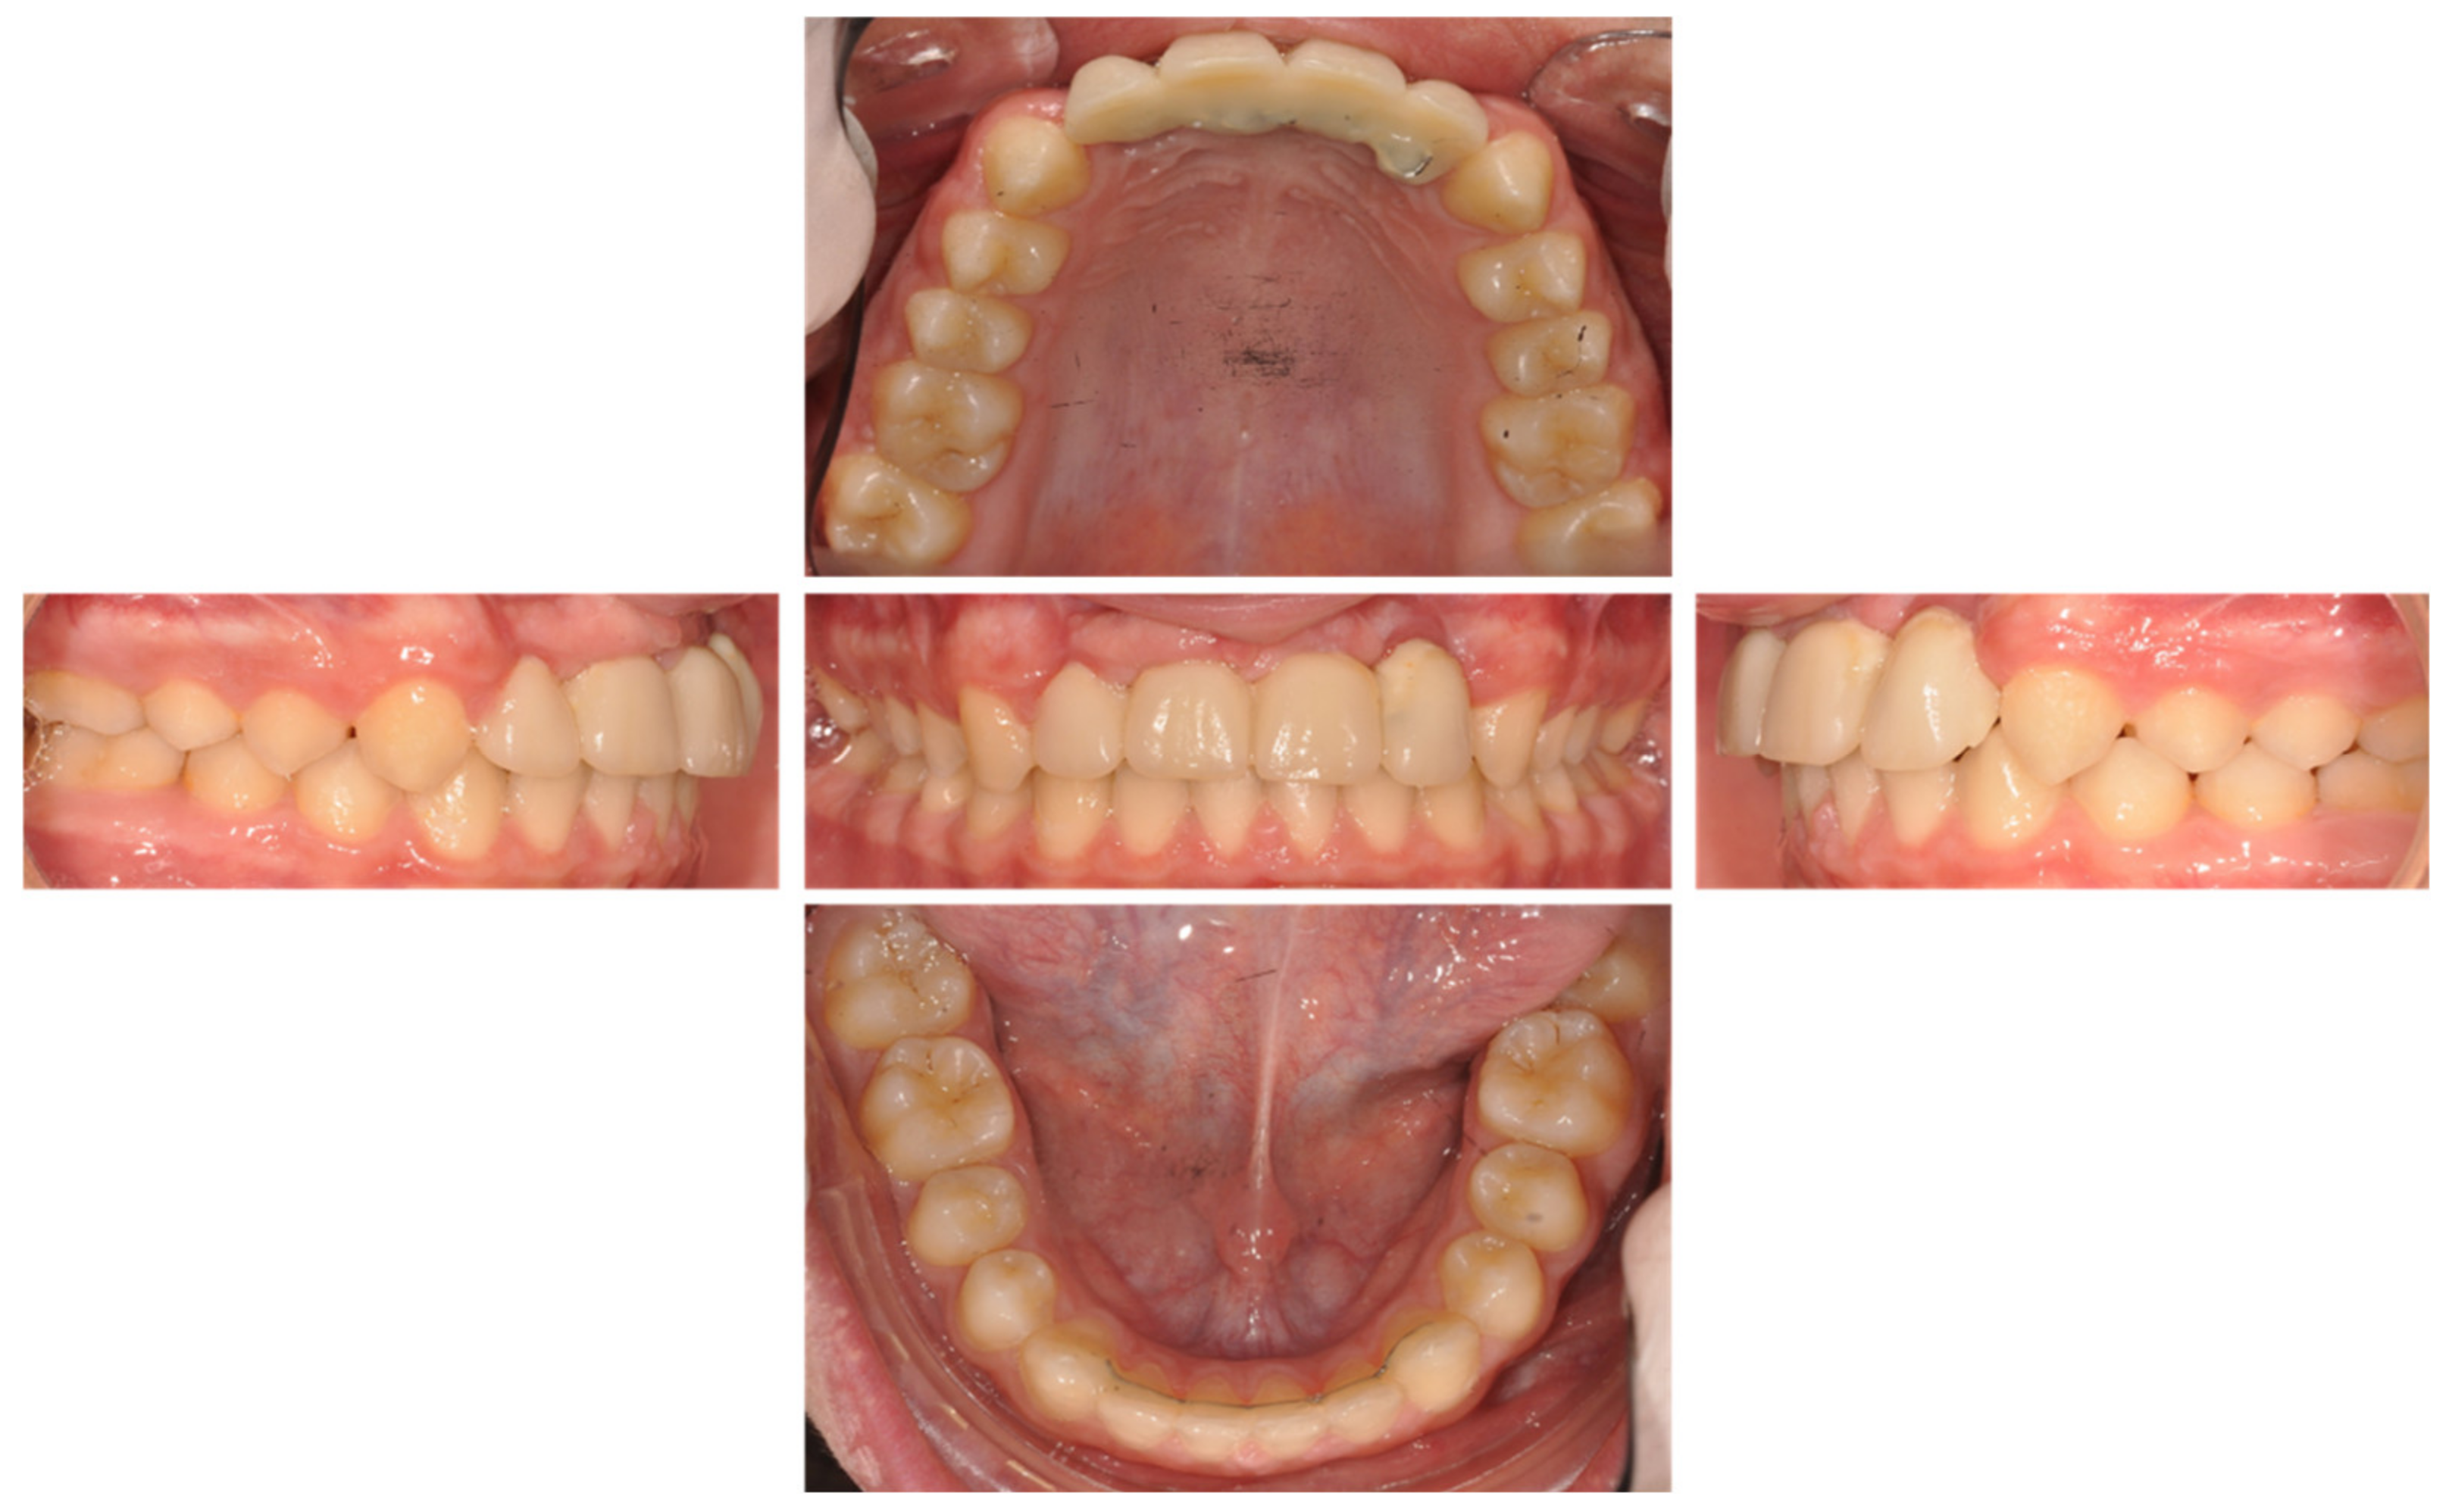

| Figure 8 | ||||